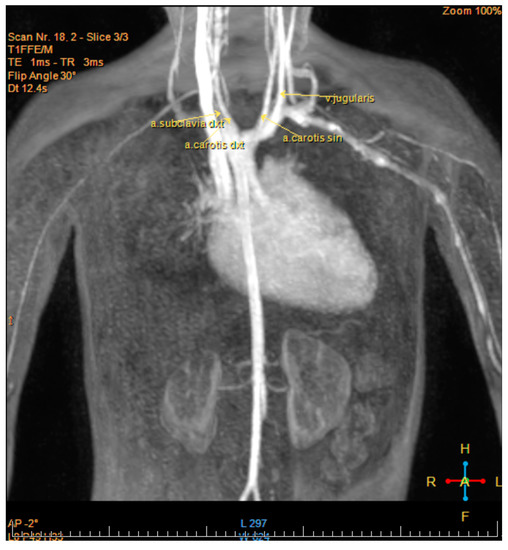

Ebstein Anomaly and Right Aortic Arch in Patient with Charge Syndrome

2. Case Report